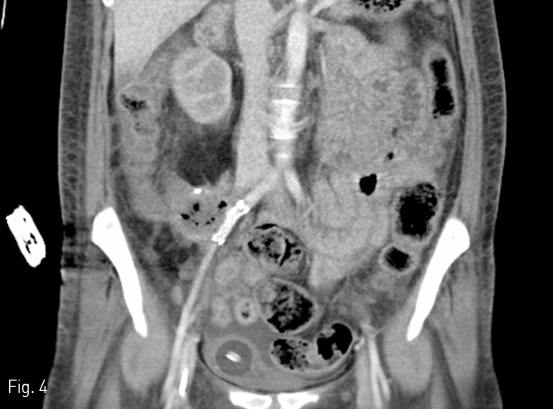

이후 혈변 등의 증상은 호전되었고, 2개월 후 추적관찰한 CT 상 stent graft는 patent 하게 유지되고 있으며 이전의 outpouching 하는 가성동맥류는 더 이상 보이지 않는다. 이식편의 air bubble 소견은 지속적으로 남아 있으나 오랜 기간 추적관찰 영상에서 변화 없이 유지되며, 임상적으로 감염을 시사하는 소견이 없는 상태이다. (Fig 4)

Fig 4

On follow up CT followed up 2 months later, the stent graft remained patent and there is no recurrence of pseudoaneurysm.